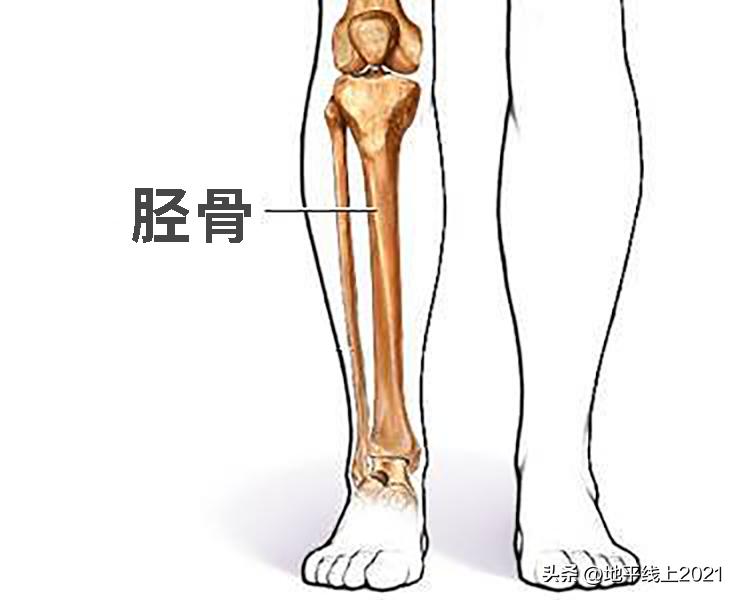

近期接诊了一位小腿骨折 (胫骨骨折) 的7岁男孩,在小区里被一个大孩子骑自行车撞倒了,虽有疼痛不适, 但过一会儿就能够继续玩耍,家长认为问题不大。 可到了晚上睡觉时,孩子说腿很疼,整晚睡得不安稳。第二天小腿还出现了轻微的肿胀,孩子不愿意下床, 到医院拍了X线片,医生诊断“胫骨骨折”。